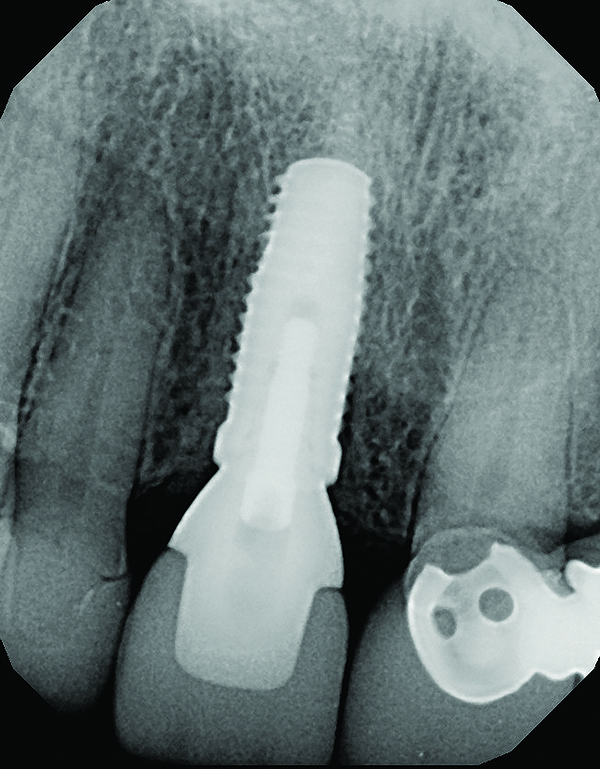

Fig 2. Periapical radiograph revealing the fractured central incisor.

Figure 2

A 63-year-old female patient presented with mobility of her right maxillary incisor, tooth No. 8, secondary to endodontic therapy (Figure 1). Her medical and dental histories were non-contributory. Clinical and radiographic evaluations revealed an 8-mm probing depth on the palatal aspect. The tooth was deemed to be fractured (Figure 2). The treatment plan accepted by the patient was for extraction, immediate implant placement, and immediate provisional restoration, if possible.